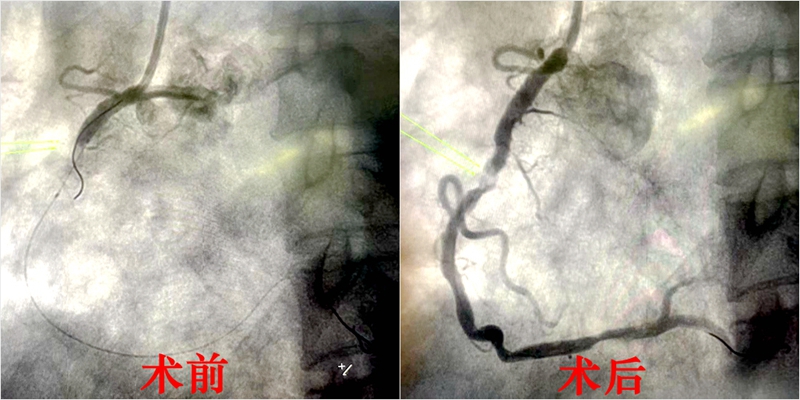

心血管内科主任阮宏标、副主任赖仙辉及主治医师陈忠武立即为叶先生实行心脏介入手术,造影显示心脏三支血管严重病变,其中右冠中段完全闭塞。救心团队火速抽出血栓,精准植入支架,最终成功救下一命。DtoW(患者进入医院大门到导丝通过血管)时间仅为12分钟,快于国际标准时间整整78分钟!

医院绿色通道秒速开通,心血管内科主任阮宏标、副主任赖仙辉再一次联手上阵,第一时间为张阿婆实行心脏介入手术。造影发现,老人心脏上粗大的右冠近段急性完全闭塞,前降支中段慢性完全闭塞。随即,救心团队在右冠抽取出长达6厘米的血栓,最终植入支架,惊险救命。